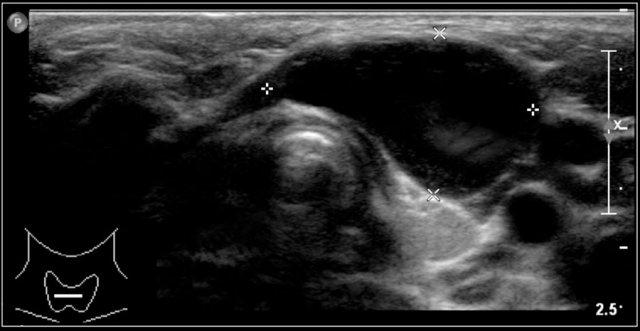

Chúng nằm dọc theo bờ trước của cơ ức đòn chũm, bên ngoài động mạch cảnh chung, và nếu ở vị trí cao hơn thì nằm giữa động mạch cảnh trong và động mạch cảnh ngoài.

Đôi khi có thể thấy dấu hiệu mỏ chim xuất hiện dưới dạng một vành cong của tổn thương hướng vào trong, nằm giữa động mạch cảnh trong và động mạch cảnh ngoài.

Trên siêu âm, chúng thường chứa các tiếng vang bên trong do mảnh vụn gây ra, bao gồm các tinh thể cholesterol.

Nang thường có thể bị nén ép, dẫn đến sự di chuyển của các thành phần bên trong.

Đây là một nang khe mang khác với vị trí điển hình nằm nông so với chỗ phân đôi động mạch cảnh.